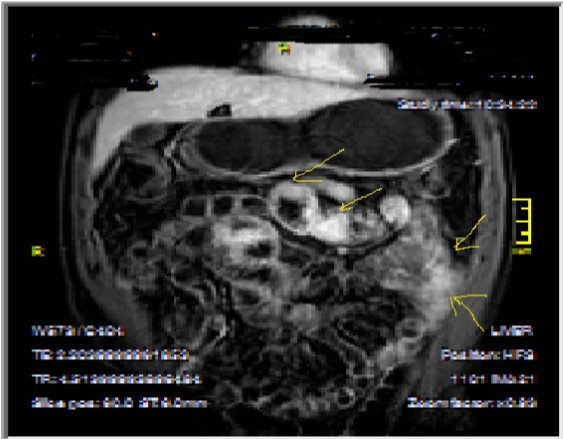

Figure 2a.Concentric luminal narrowing, mural and transmural involvement of terminal ileum due to Crohn’s disease in T2W coronal sequence after OCA application.

Figure 2b.Curvi-lineer, diffuse peripheral enhancing bowel wall in the terminal ileum on axial T1W post-contrast image.

Figure 3a-3b-3c.Diffuse mucosal involvement and extreme luminal narrowing in the terminal ileum due to Crohn’s disease on T2W coronal sequence after OCA administration, stricture and string sign near ileo-ceccal valve in Figure 3b.